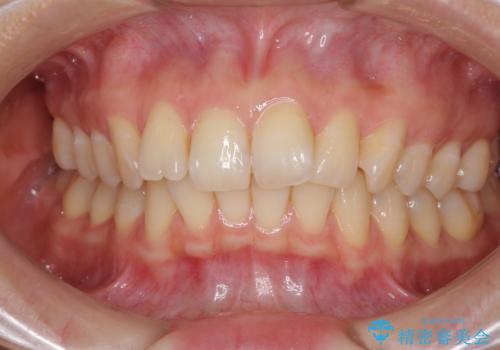

- 前歯の叢生と口元の閉じにくさを気にして来院された患者様です。

奥歯の咬み合わせを見ると、上顎が下顎に対して相対的に前方にありました。

カリエールディスタライザーを併用したことで、確実かつ短期間で治療を終えることができました。